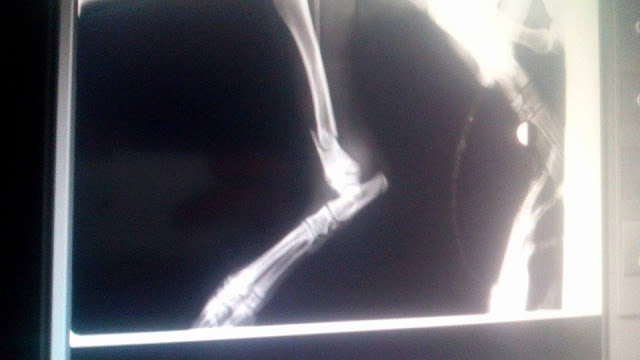

1 καταγμα η Κλειω και 3 ο Buter στα ποδια

Η Κλειω έχει συντριπτικό κάταγμα μηριαιου με παρεκτοπηση.

Θα πρεπει να γίνει χειρουργική αναταξη με πλάκα.

Ο Butter έχει συντριπτικό κάταγμα μηριαιου με παρεκτοπηση και αμφοτεροπλευρο κάταγμα κνημης περονης. Ιδια διαδικασία αναταξης.

Ειναι στην ουσια 4 χειρουργεια και το κόστος είναι 800 ευρώ.